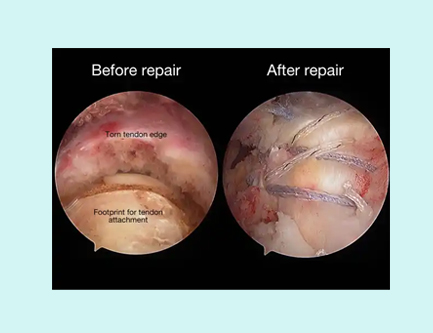

KEY HOLE SURGERY (ARTHROSCOPY) IS AN ADVANCED TREATMENT OPTION WHICH WILL REDUCE POSTOPERATIVE PAIN.

MOST COMMON INJURY IN ELDERLY IS CUFF TEAR WHICH IS AGE RELATED MOST OF THE TIMES. THIS REQUIRES REPAIR FOR NORMAL FUNCTIONING OF SHOULDER.